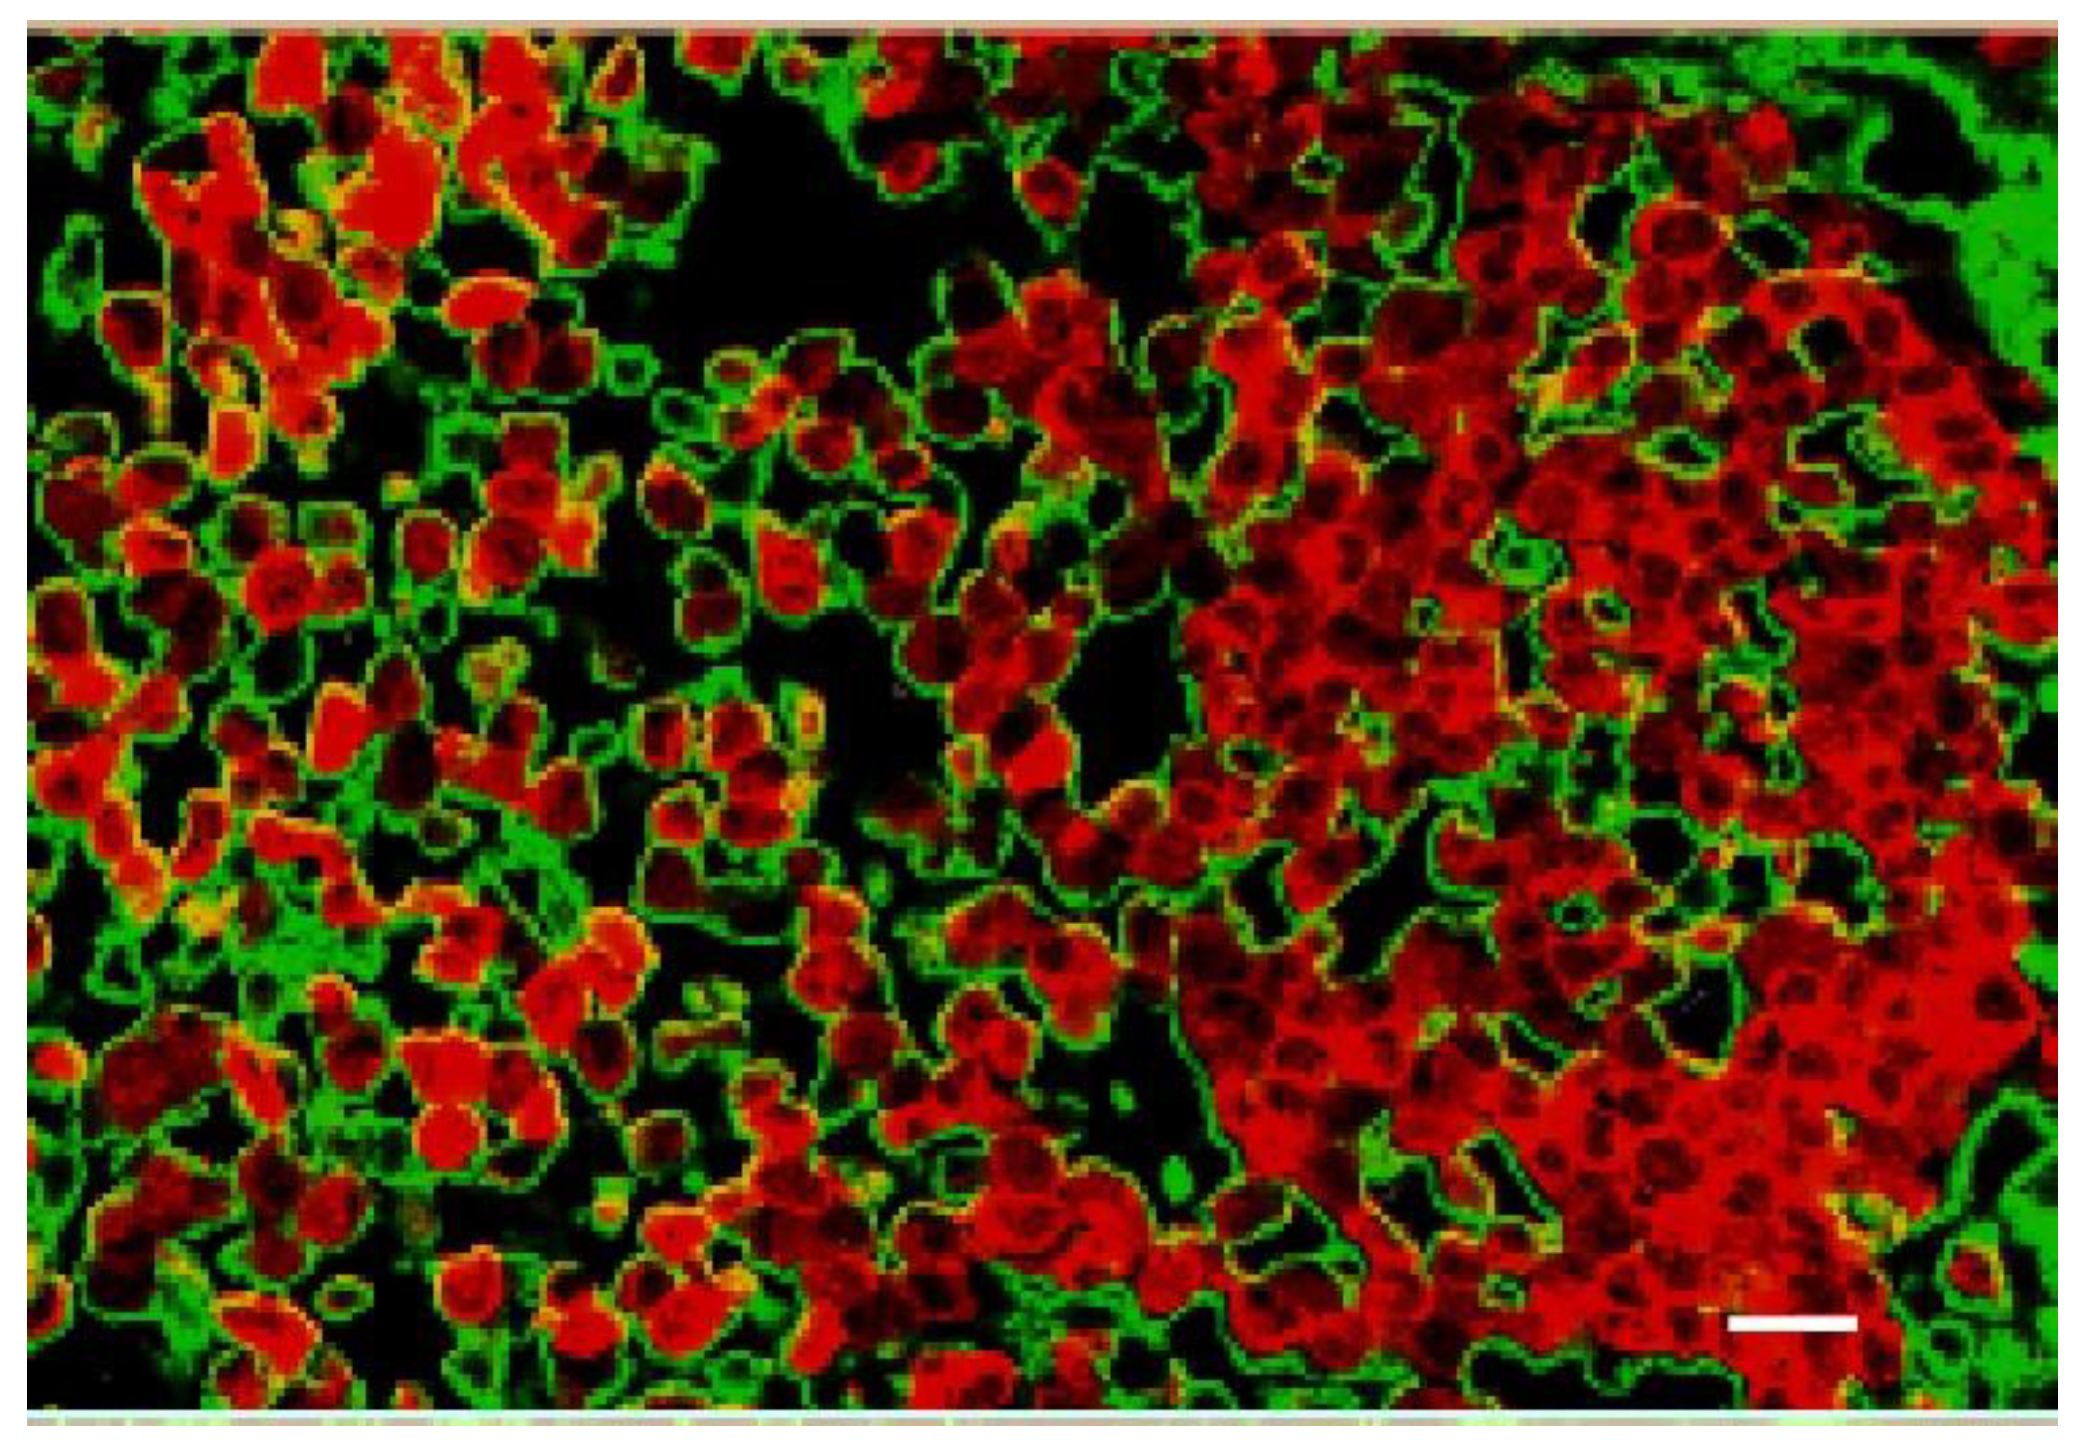

1.7. Iodine Nanoparticle Targeting

1.8. Iodine-Enhanced Radiotherapy of Brain Metastases

1.9. Iodine Nanoparticle Targeting to Brain Metastases